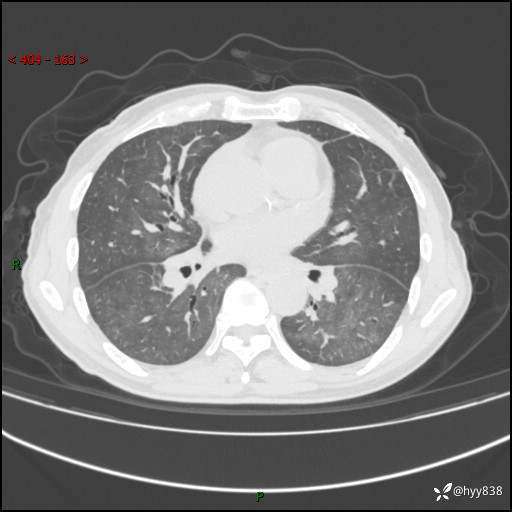

肺结节入院,CT却发现肺部弥漫性病变,what happened---(有结果)

主诉:检查发现左上肺结节4天

简要病史:患者于2024-01-15当地市人民医院胸部CT提示:左肺上叶(69)结节,最大截面约1.0 x 1.2cm,肿瘤病变待排。现患者活动后呼吸困难,自述平地行走200m后胸闷气喘,不伴咳嗽咳痰、头晕、恶心、呕吐等不适,未行特殊处理。现患者为求进一步治疗,于我院就诊,门诊拟“左上肺结节”收入院。 自患病以来患者食欲差,精神、睡眠尚可,大小便正常,体重近1月来下降5kg左右,体力明显减轻。

辅助检查:CT

胸部CT平扫

不是讨论肺部结节